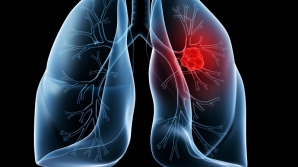

Cât de periculos este să faci grătar în aer liber? Toxinele pot provoca cancer pulmonar sau modificarea ADN